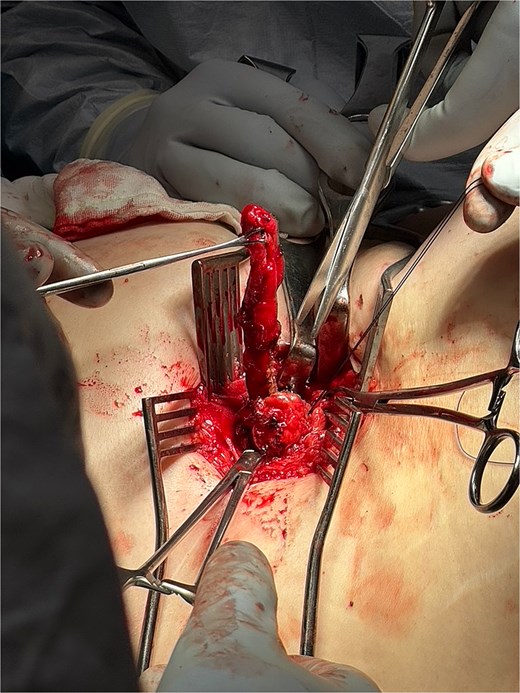

The operation utilized a left lateral position and posterior approach using the same right nephrectomy scar. A 3-cm posterior abdominal wall hernia was identified, hernial sac defined, and peritoneum opened (Fig. 4). The appendix showed no evidence of perforation, and the base was tied off using 0-vicryl, then excised (Figs 5 and 6). The external oblique fascial plane was defined and identified to be healthy, then closed with 0 Polydiaxanone (PDS) suture and washed (Fig. 7). A Phasix® biological mesh was placed onlay and anchored with 2–0 Prolene to the subcostal and external oblique fascia (Fig. 8). Postoperatively, the patient received one additional day of intravenous antibiotics and was discharged with an abdominal binder and 5-day course of oral Augmentin-Duo Forte.

Intraoperative image showing entry into the posterior abdominal wall hernia using the same right nephrectomy scar. The peritoneum is opened and appendix is isolated.